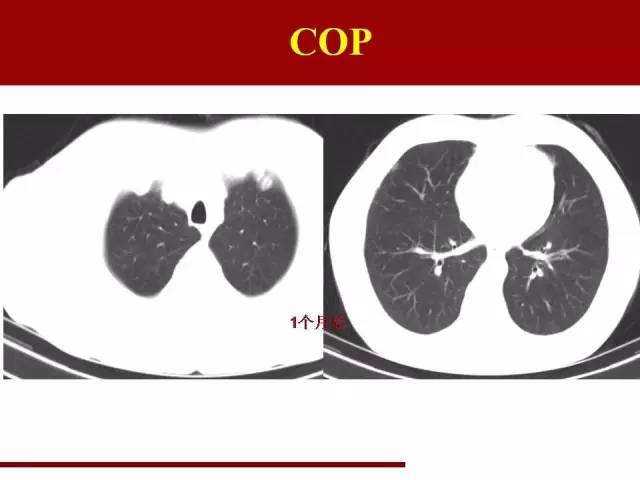

下面是OP,OP在近些年逐渐被重视,讨论的也很多,我就一笔带过